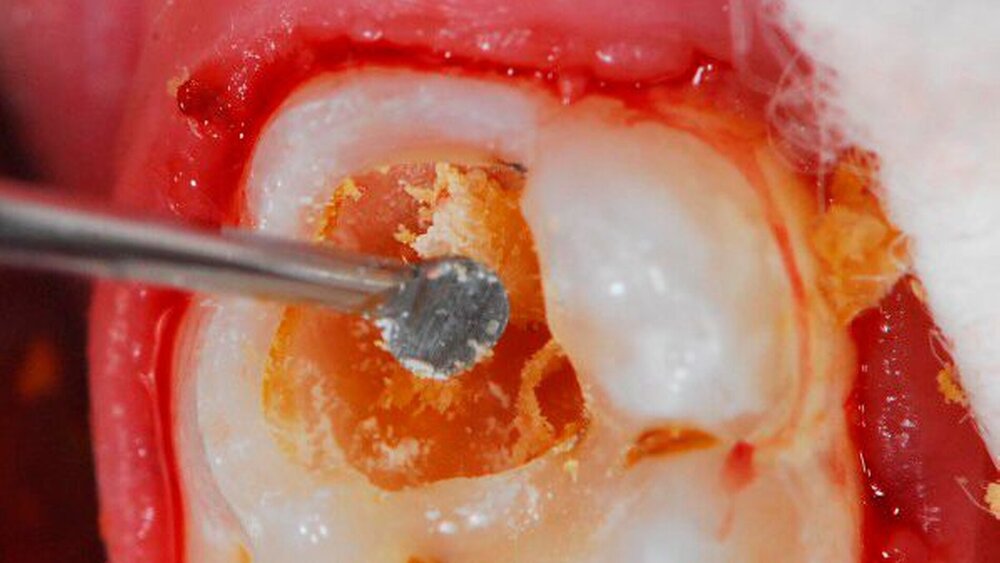

Um den Endpunkt der Kariesexkavation objektivieren zu können, wird der Einsatz von sich selbstlimitierenden oder fluoreszenzunterstützenden Instrumenten diskutiert. Dazu zählten etwa Polymerbohrer, deren Härte sich am erweichten nicht infizierten, aber remineralisierbaren Dentin orientiert. Für das Vorgehen der fluoreszenzunterstützten Karieserkennung und -entfernung sind ebenfalls entsprechende Systeme auf dem Dentalmarkt verfügbar. Die Verwendung von Handexkavatoren erlaubt demnach gerade im Milchgebiss eine substanz- und pulpaschonende Exkavation.

Für die definitive Restauration und Inaktivierung des kariösen Prozesses ist den Autoren zufolge entscheidend, dass der Kavitätenrand zirkulär eine adhäsive Versiegelung erlaubt. Dabei stellt die selektive Kariesexkavation (siehe Bilderstrecke) die Therapie der Wahl dar.